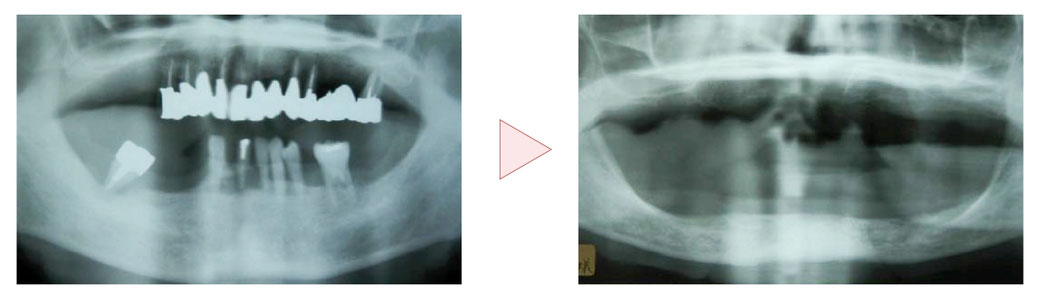

治療用義歯(治療中の仮の入れ歯)を入れたその日から、見た目も良くなり、美味しく食事をしながら治療を続けられます。

最短2週間で治療用義歯を装着でき、歯ぐきや噛み合わせの状態に合わせて仮の入れ歯を調整しながら治療を進めます。